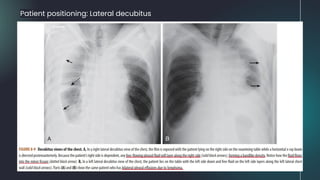

Patient positioning: Lateral decubitus

● When the hemithorax contains about 2 L of fluid, the entire

hemithorax will be opacified.

● As fluid fills the pleural space, the lung tends to undergo

passive collapse (atelectasis).

● Large effusions can act like a mass and displace the heart

and trachea away from the side of opacification.